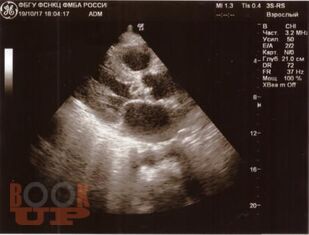

Инфекционный эндокардит

В настоящем учебном пособии освещены вопросы современных представлений об инфекционном эндокардите: определение, классификации, основные принципы диагностики и лечения. Имеются тестовые задания и ситуационные задачи для самоконтроля знаний.